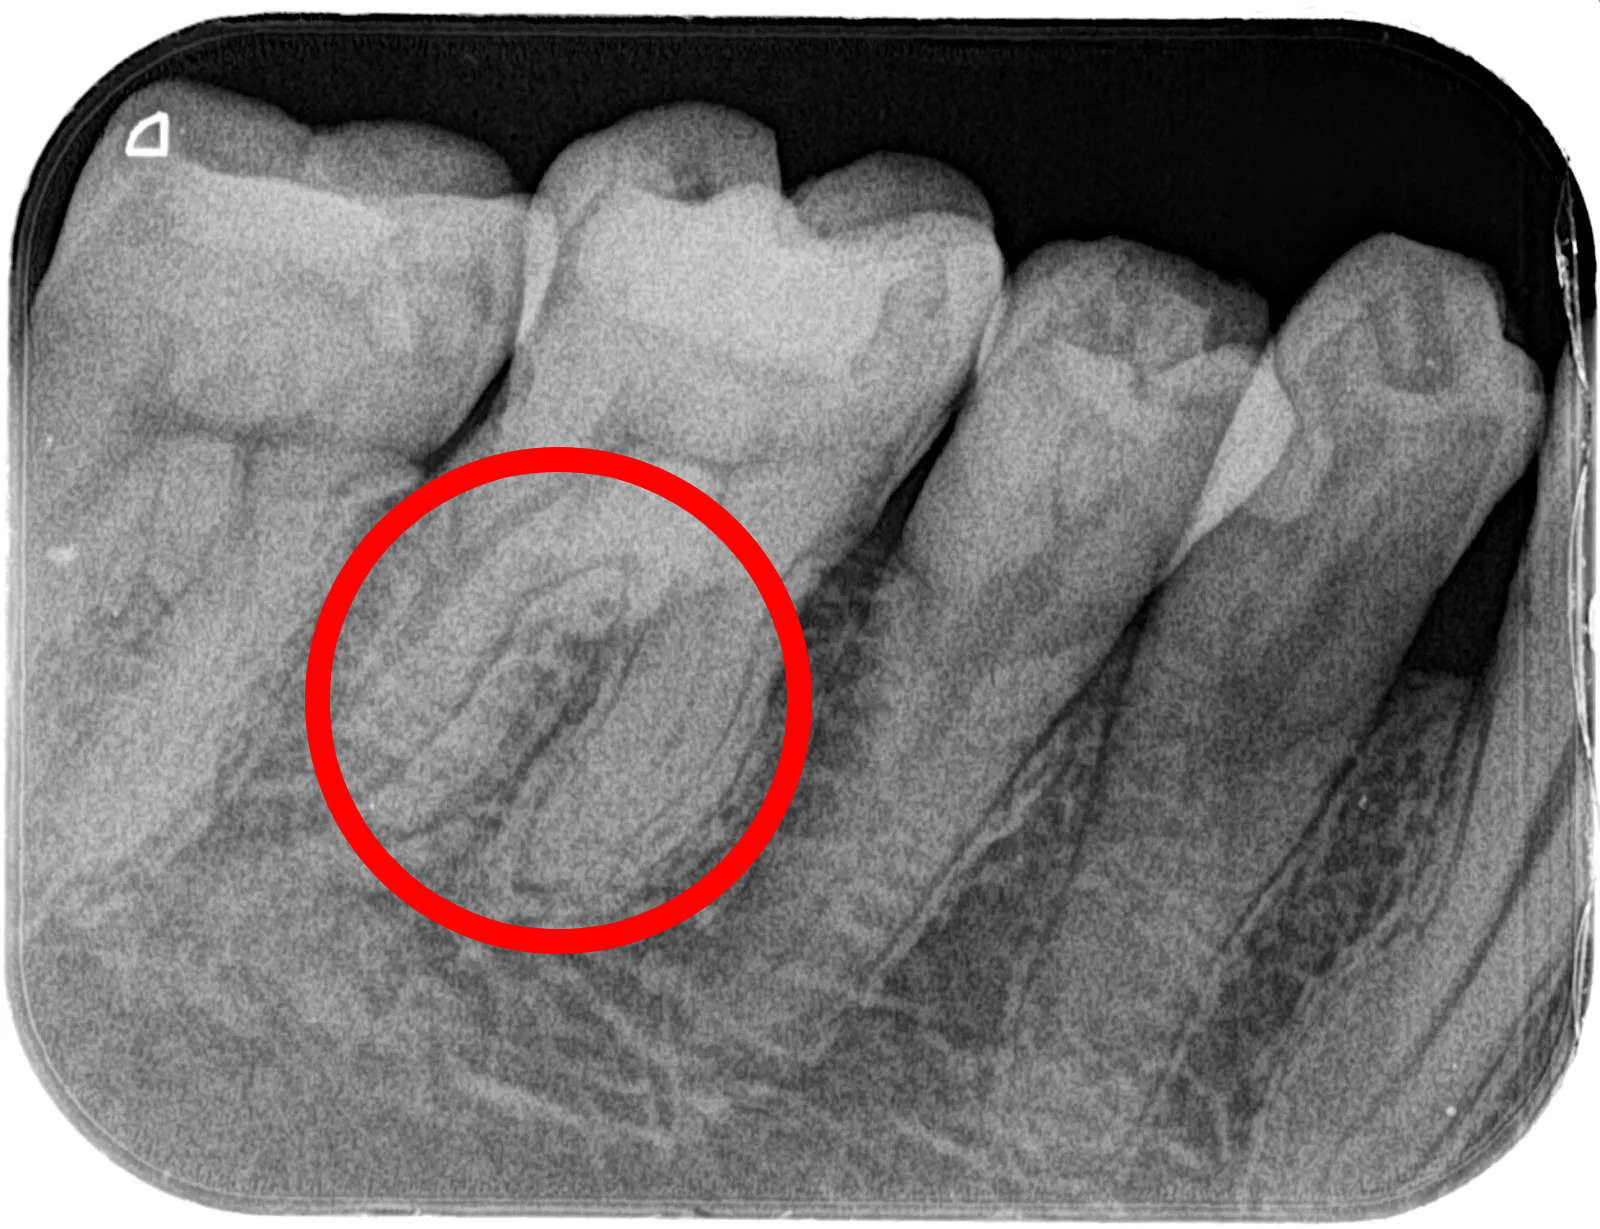

なお、下の画像をご覧ください。歯の内部に黒く細い線が見える部分が「根管」です。

根管は非常に細く、湾曲し枝分かれしているところも多く、その複雑さが一目でわかると思います。